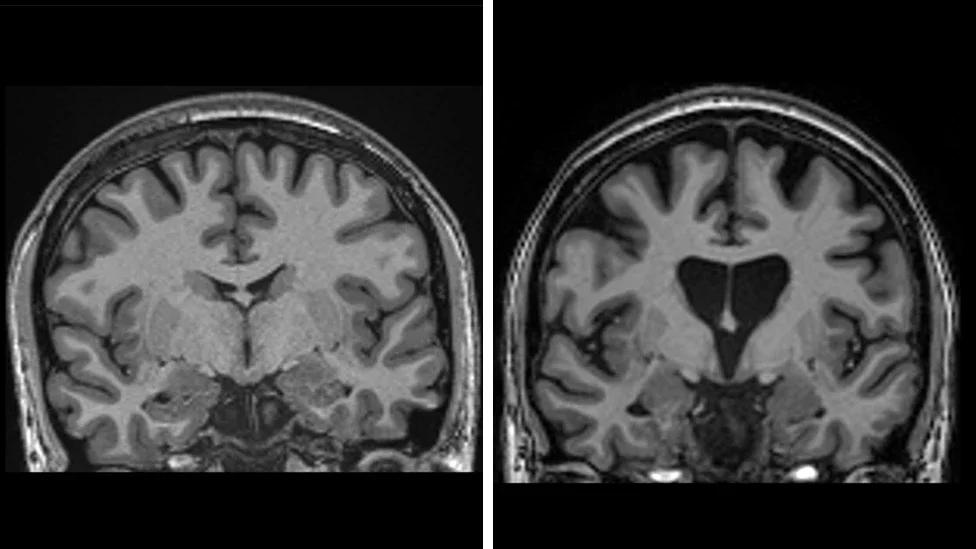

The brain scan on the left shows a healthy brain, while the one on the right shows a loss of brain matter due to the death of neurons